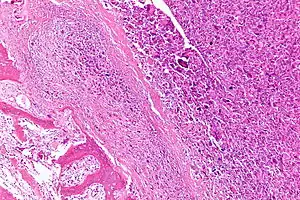

| Intermediate-magnification micrograph of an osteosarcoma (center and right of image) adjacent to non-malignant bone (left-bottom of image): The top-right of the image has poorly differentiated tumor. Osteoid with a high density of malignant cells is seen between the non-malignant bone and poorly differentiated tumor (H&E stain). | |

Microscopically: The characteristic feature of osteosarcoma is presence of osteoid (bone formation) within the tumor. Tumor cells are very pleomorphic (anaplastic), some are giant, numerous atypical mitoses. These cells produce osteoid describing irregular trabeculae (amorphous, eosinophilic/pink) with or without central calcification (hematoxylinophilic/blue, granular)—tumor bone. Tumor cells are included in the osteoid matrix. Depending on the features of the tumor cells present (whether they resemble bone cells, cartilage cells, or fibroblast cells), the tumor can be subclassified. Osteosarcomas may exhibit multinucleated osteoclast-like giant cells.[20]